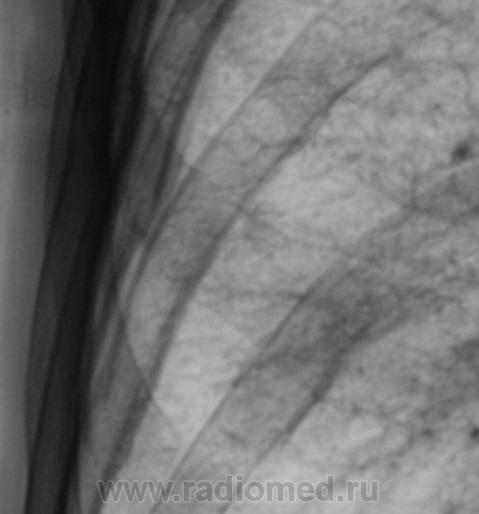

2 - прицельные Т-граммы на втором контроле : думаете патологические переломы (или уверены), травматический анамнез?

"Травматического" анамнеза нет.

Ответы есть. Пациенту выставлена "четверка". Проведено шесть курсов "химии".

Все это было не в нашем ЛПУ - ЦРБ, а в областной туббольнице. Знаю только, что после биопсии диагноз был изменен, биопсия была также из лимфоузлов,  да и пациенту сильно похужело, сейчас уже не встает...